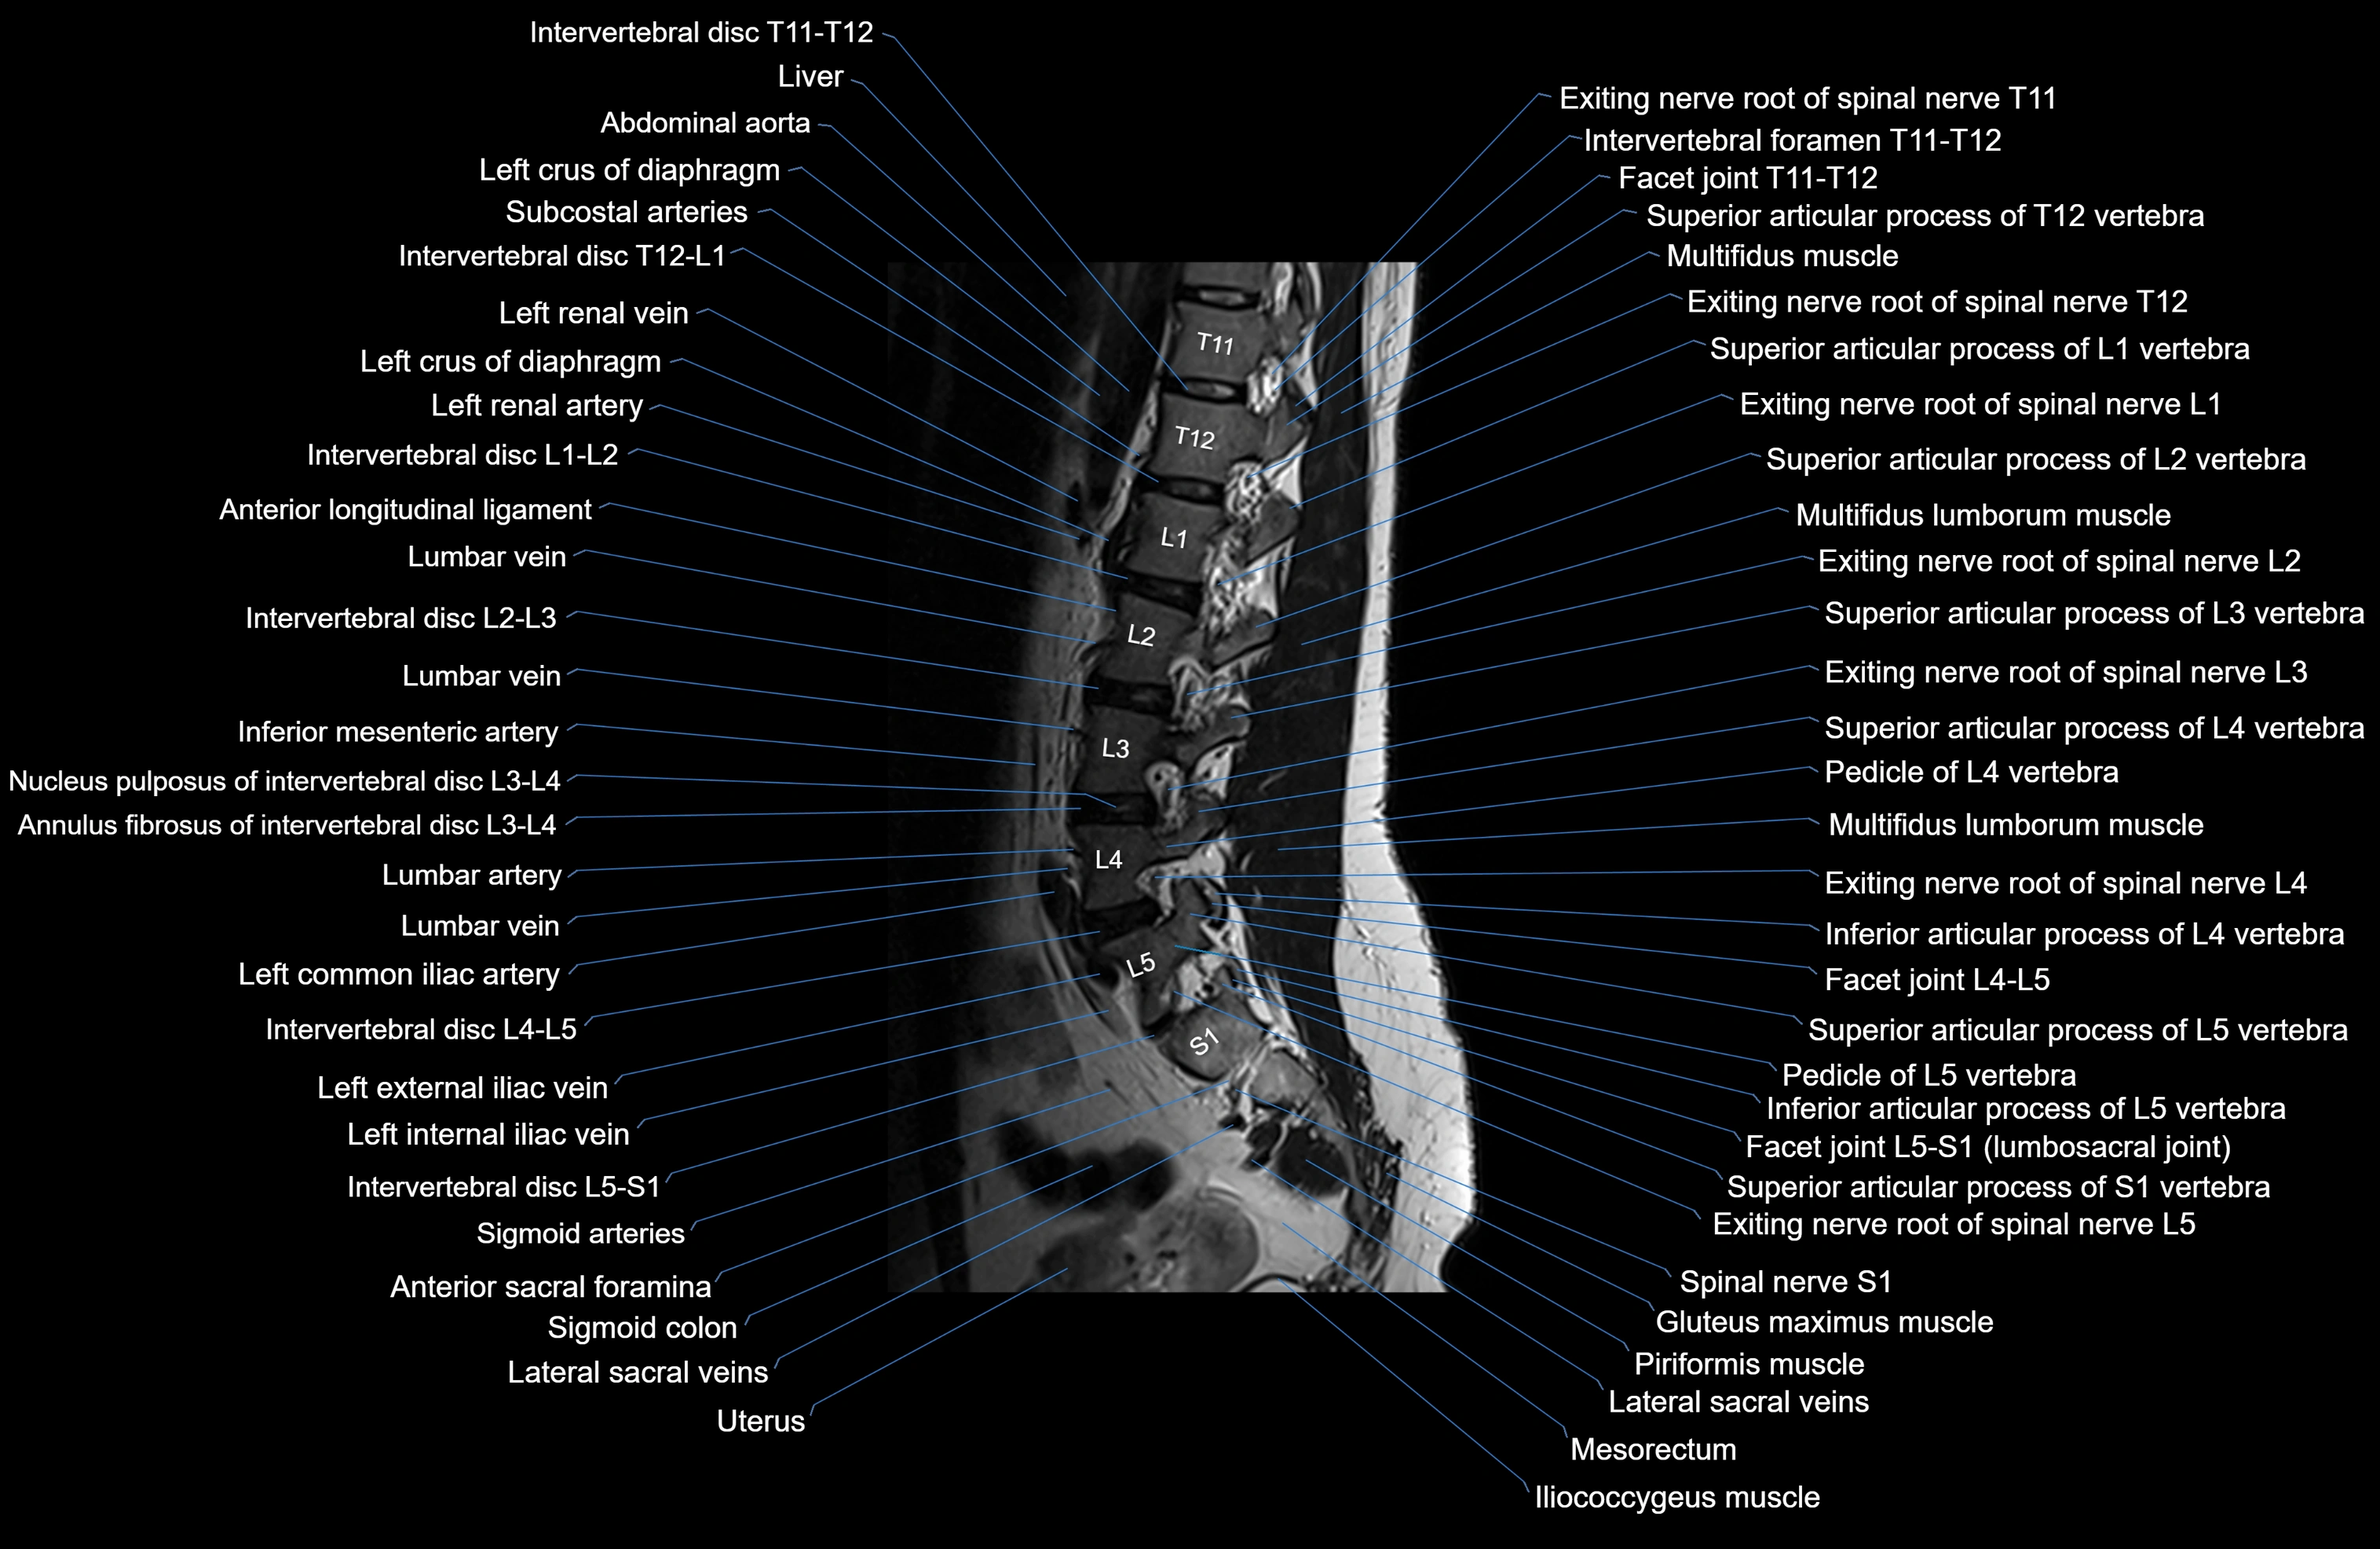

MRI images